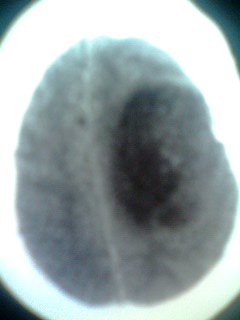

女。65岁头疼,多发硬化病史5年,近十余天加重

巨大囊性占位,白质水肿确不明显,定性?

囊实性占位,考虑胶质瘤可能性大,建议增强.

北京天坛,结论:多发硬化